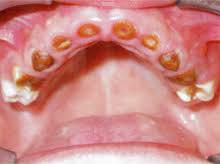

Kariess- hroniska infekcijas slimība

Tā ātri vien sabojā bērna zobus, tāpēc rada veselības problēmas.